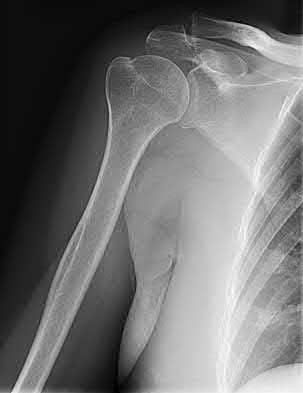

2. # A 35-year-old woman is involved in a head-on collision while driving. Initial radiographs are shown in Figures 8a and 8b. Injury to what vessel increases the risk for osteonecrosis of the injured bone?

5. Artery of the tarsal sinus Corrent answer: 4

The patient has a Hawkins type III talar neck fracture-dislocation with a risk of osteonecrosis ranging from 69% to 100%. Anatomic studies have shown that the artery of the tarsal canal supplies the lateral two thirds of the talar body.

The other vessels listed provide no significant contribution to the talus.